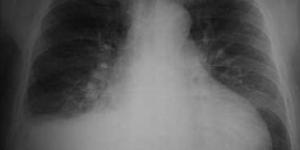

Descubrir que tenemos una mancha en los pulmones puede causarnos gran inquietud, sin embargo son varias las razones que producen esta condición y, al contrario de lo que se piensa, no todas están vinculadas con una formación tumoral.

La radiografía de tórax o la tomografía son los exámenes empleados habitualmente...